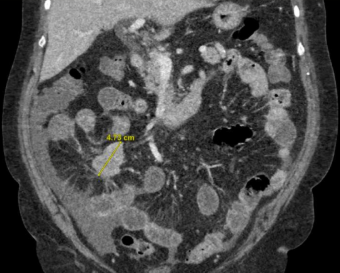

Image showing infiltrating small bowel carcinoid with tethering of bowel and mesentery (spokewheel sign) suggestive of desmoplastic reaction

Several differentials like gastroenteritis, colitis & diverticulitis were considered. CECT abdomen/ pelvis in the ED revealed infiltrating small bowel carcinoid with desmoplastic mesenteric involvement.